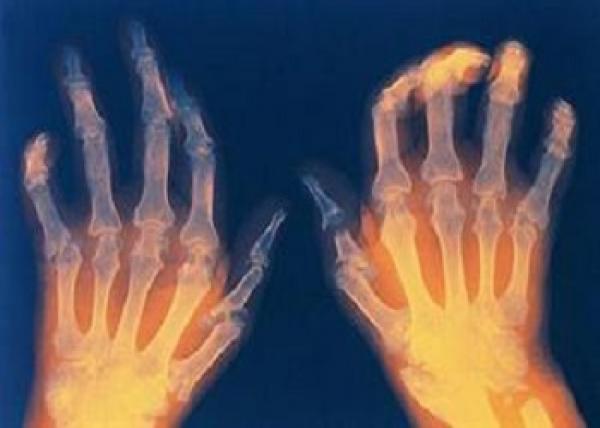

كشف فريق من الباحثين الأوربيين، عن معلومات جديدة وخطيرة بشأن مرض التهاب المفاصل الروماتويدى، أحد الأمراض المناعية المزمنة التى تهاجم المفاصل الثابتة بالجسم، وتصيب حوالى 1% من تعداد سكان العالم.